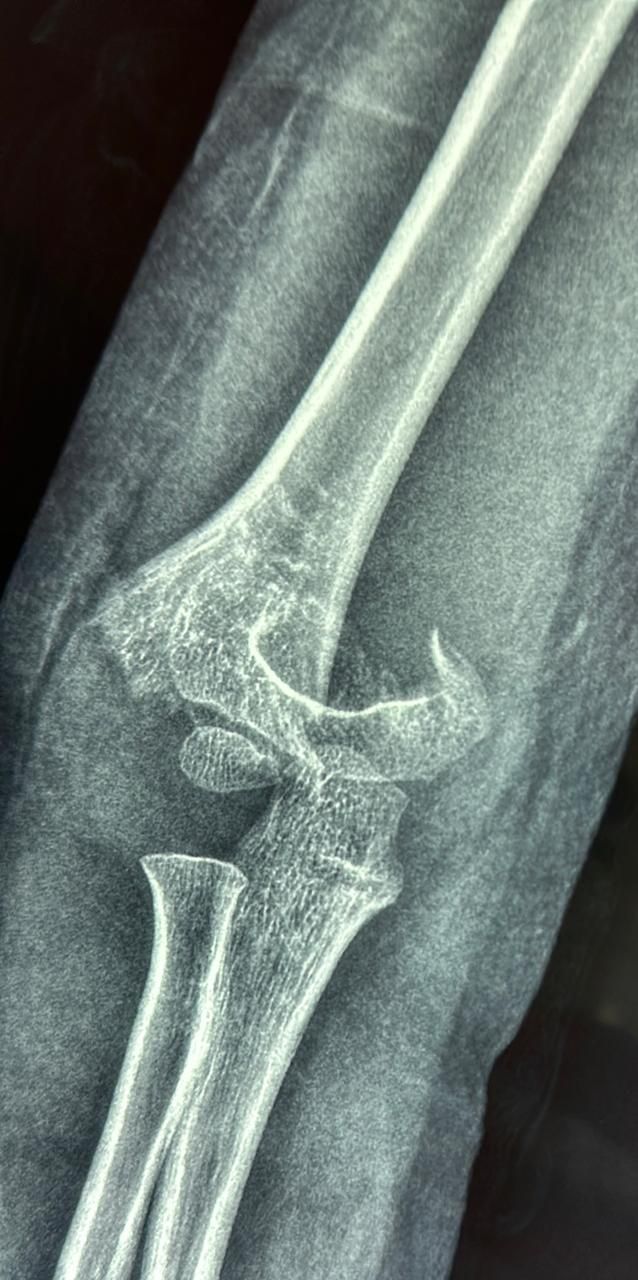

Cada caso es valorado a profundidad para proponer tratamientos conservadores (rehabilitación, ejercicios, ortesis) o procedimientos quirúrgicos cuando son necesarios, como artroplastías (colocación de prótesis articulares) o cirugías mínimamente invasivas como la artroscopía.